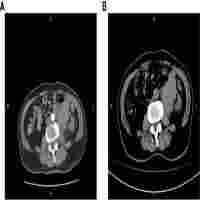

| Abstract | Pulmonary sarcomatoid carcinoma (PSC) is a rare subtype of non-small cell lung cancer with high malignancy and poor prognosis. Chemotherapy or radiotherapy do not usually provide satisfactory results in patients with PSC, especially in those with advanced-stage cancer. Targeted therapy and immunotherapy are more precise therapies that may be effective in the treatment of PSC; however, further research is needed. Here, we present a case of stage III PSC with obstructive atelectasis, which is more challenging and hinders treatment. Treatment with the PD-1 inhibitor camrelizumab and transbronchial cryoablation showed significant clinical efficacy. This type of combined treatment has not been reported previously for PSC. Thus, this case may provide a valuable reference for future clinical practice and research. |